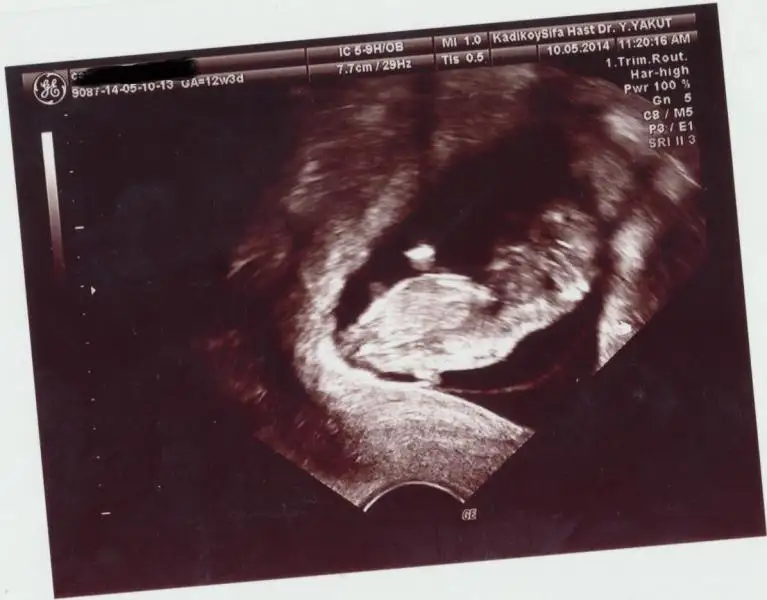

12+5 te gidicez bide o zaman resim atarim burda net degilse :)

bebek çok küçük o yüzden belli değil

Bizimkini de tahmin edinn noluurrr :) çok merak ediyoruz ultrason 12+3 de çekildi.Eki Görüntüle 1127216

yorum yapılmamış yorumlarınızı merak ediyorum yorum yapacak arkadaşlar varmı :)arkadaşlar 11hafta 4 günlüğüz cisiyet tahmini yaparmısınız :)